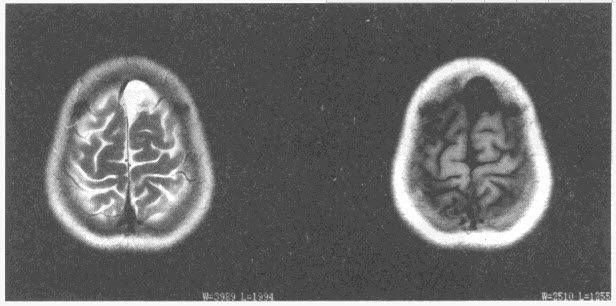

患者,女,49岁,头痛,MRI表现如下图,最可能的诊断是()

A:硬膜下血肿

B:硬膜下积液

C:Dandy-Walker综合征

D:脑积水

E:蛛网膜囊肿